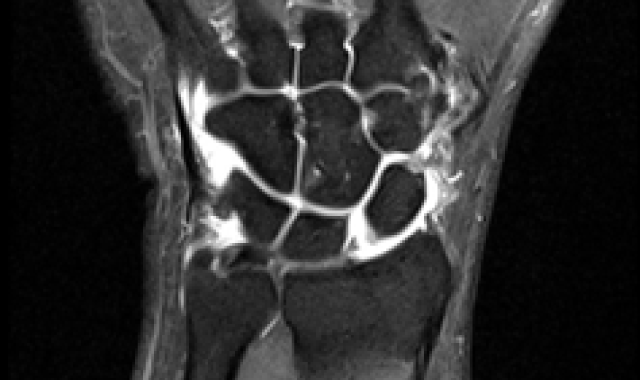

주상월상인대파열 진단법

X-ray 진단으로 보이지 않을 경우

→ 초음파, MRI 영상 검사

주상골, 월상골 사이 인대는 아주 작아 MRI 로 진단이 어려운 경우

→ 손목관절 내시경을 통해 진단

주상월상인대파열 MRI영상